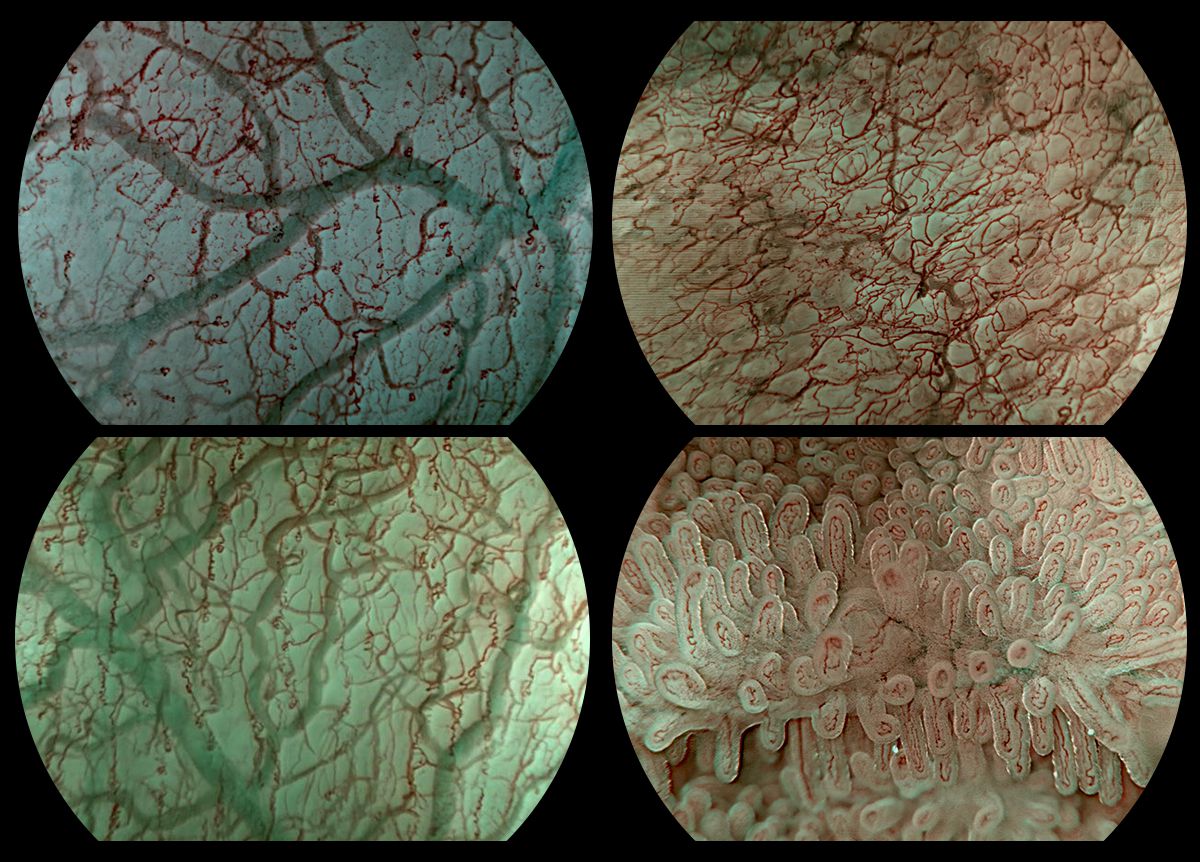

This year, our exhibition focus was the future of early cancer screening, aiming to make the process faster, clearer, and more accessible for everyone. We were thrilled by the overwhelming response to our latest advancements in endoscopic imaging:

Meets Health: This system delivers stunning, ultra-high-definition 4K resolution, providing clinicians with unprecedented visual detail. This superior clarity is crucial for distinguishing subtle tissue changes, offering a new benchmark in diagnostic accuracy for early-stage pathology.